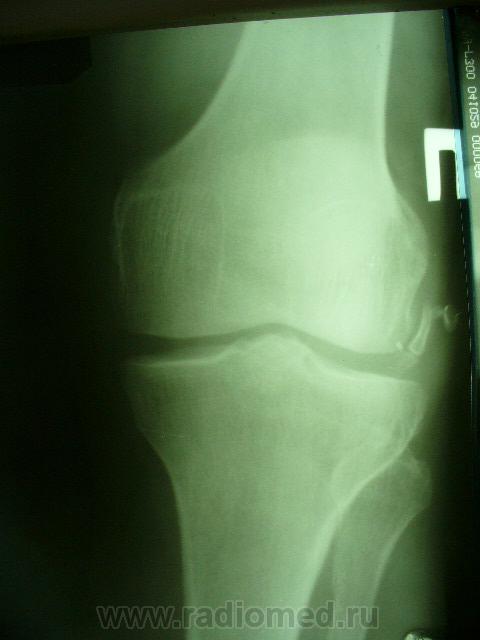

Уважаемые коллеги. Не так давно на странице сайта обсуждалась тема гипердиагностики ДОА. Хотелось бы увидеть ваше мнение по поводу наличия/отсутствия ДОА на представленных снимках. Лет 8 назад попал в автодорожку где-то в другом регионе, там же лечился в НИИТО (со слов, т.к. документов никаких нет) и там же наблюдался с DS: ДОА правого к/с IIст. Переехал в наш регион и решил пройти МСЭК для получения группы инвалидности. Снимки перевернуты, чтобы скрыть маркировку. Так есть ли ДОА?

Есть. Но 1 й ст. обоих к.с.

Едва заметное сужение суставной щели только в левом к/с. На каком основании ДОА?

На мой взгляд - "норма".

Латерализация обоих надколенников, мелкий остеофит по верхнему краю правого надколенника, вытянутость и заострение межмыщелковых отростков левой б/б кости.

Прямая проекция сделана одним лучем на одной пленке, это я их "разделил". Может, из-за этого латерализация? Остеофит левого надколенника есть, никуда не денешься, но ставят артроз (обезображивающий по Рейнбергу) справа.

Вот что хотелось бы уточнить---а что это у нас с межмыщелковыми возвышениями справа???? а что это за окостенение по наружному контуру латерального мыщелка бедра??? ТРАВМА В АНАМНЕЗЕ!!!! Так что - справа - норма? Извините - не уверен. Група не только по снимкам определяется...функция тоже учитывается. А если сделать пару снимков для оценки межмыщелкового углубления и этих самых возвышений.

Выбирай, не выбирай..., а получается только гетерогенное окостенение у внутреннего надмыщелка правой бедренной кости. А с инвалидностью? Косинская как раз и работала в Ленинградском институте экспертизы трудоспособности инвалидов: 2 ст. = 2гр., 3 ст. = 1 гр., в данном случае - никакой группы. Молодцы травматологи, вылечили человека в НИИТОУлыбаюсь!

Нет проблем, пускай обосновывают артроз по своим травматологическим (клиническим) критериям. КТ/МРТ, артроскопия, можно запрос в приснопамятный НИИ сделать. Достоверных, "неубиваемых" рентгенологических признаков артроза нет.

Все правильно замечено. Это, конечно не пальцы, а дополнительные фрагменты костной структуры. Была травма, больной лечился в ИТО. Вероятно, это окостеневшие фрагменты связок, хряща или чего там еще. И межмыщелковое возвышение "изгрызано", м.б. был перелом верхушек. Но ведь это все это не является R- признаками ДОА. Цель демонстрации - выяснить, есть ли рентгеновcкие признаки обезображивающего остеоартроза?